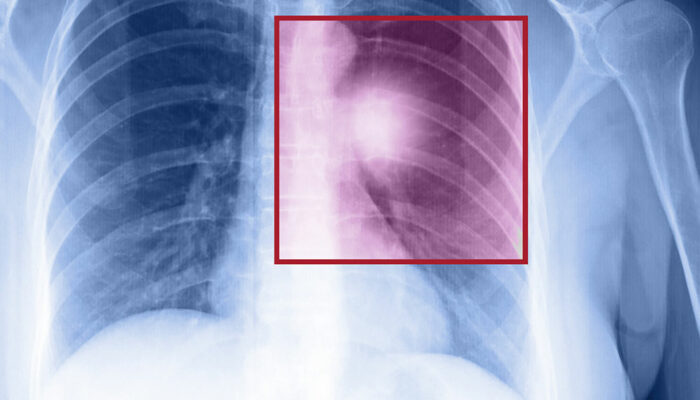

- Chest X-ray which provides detailed images of the lungs.